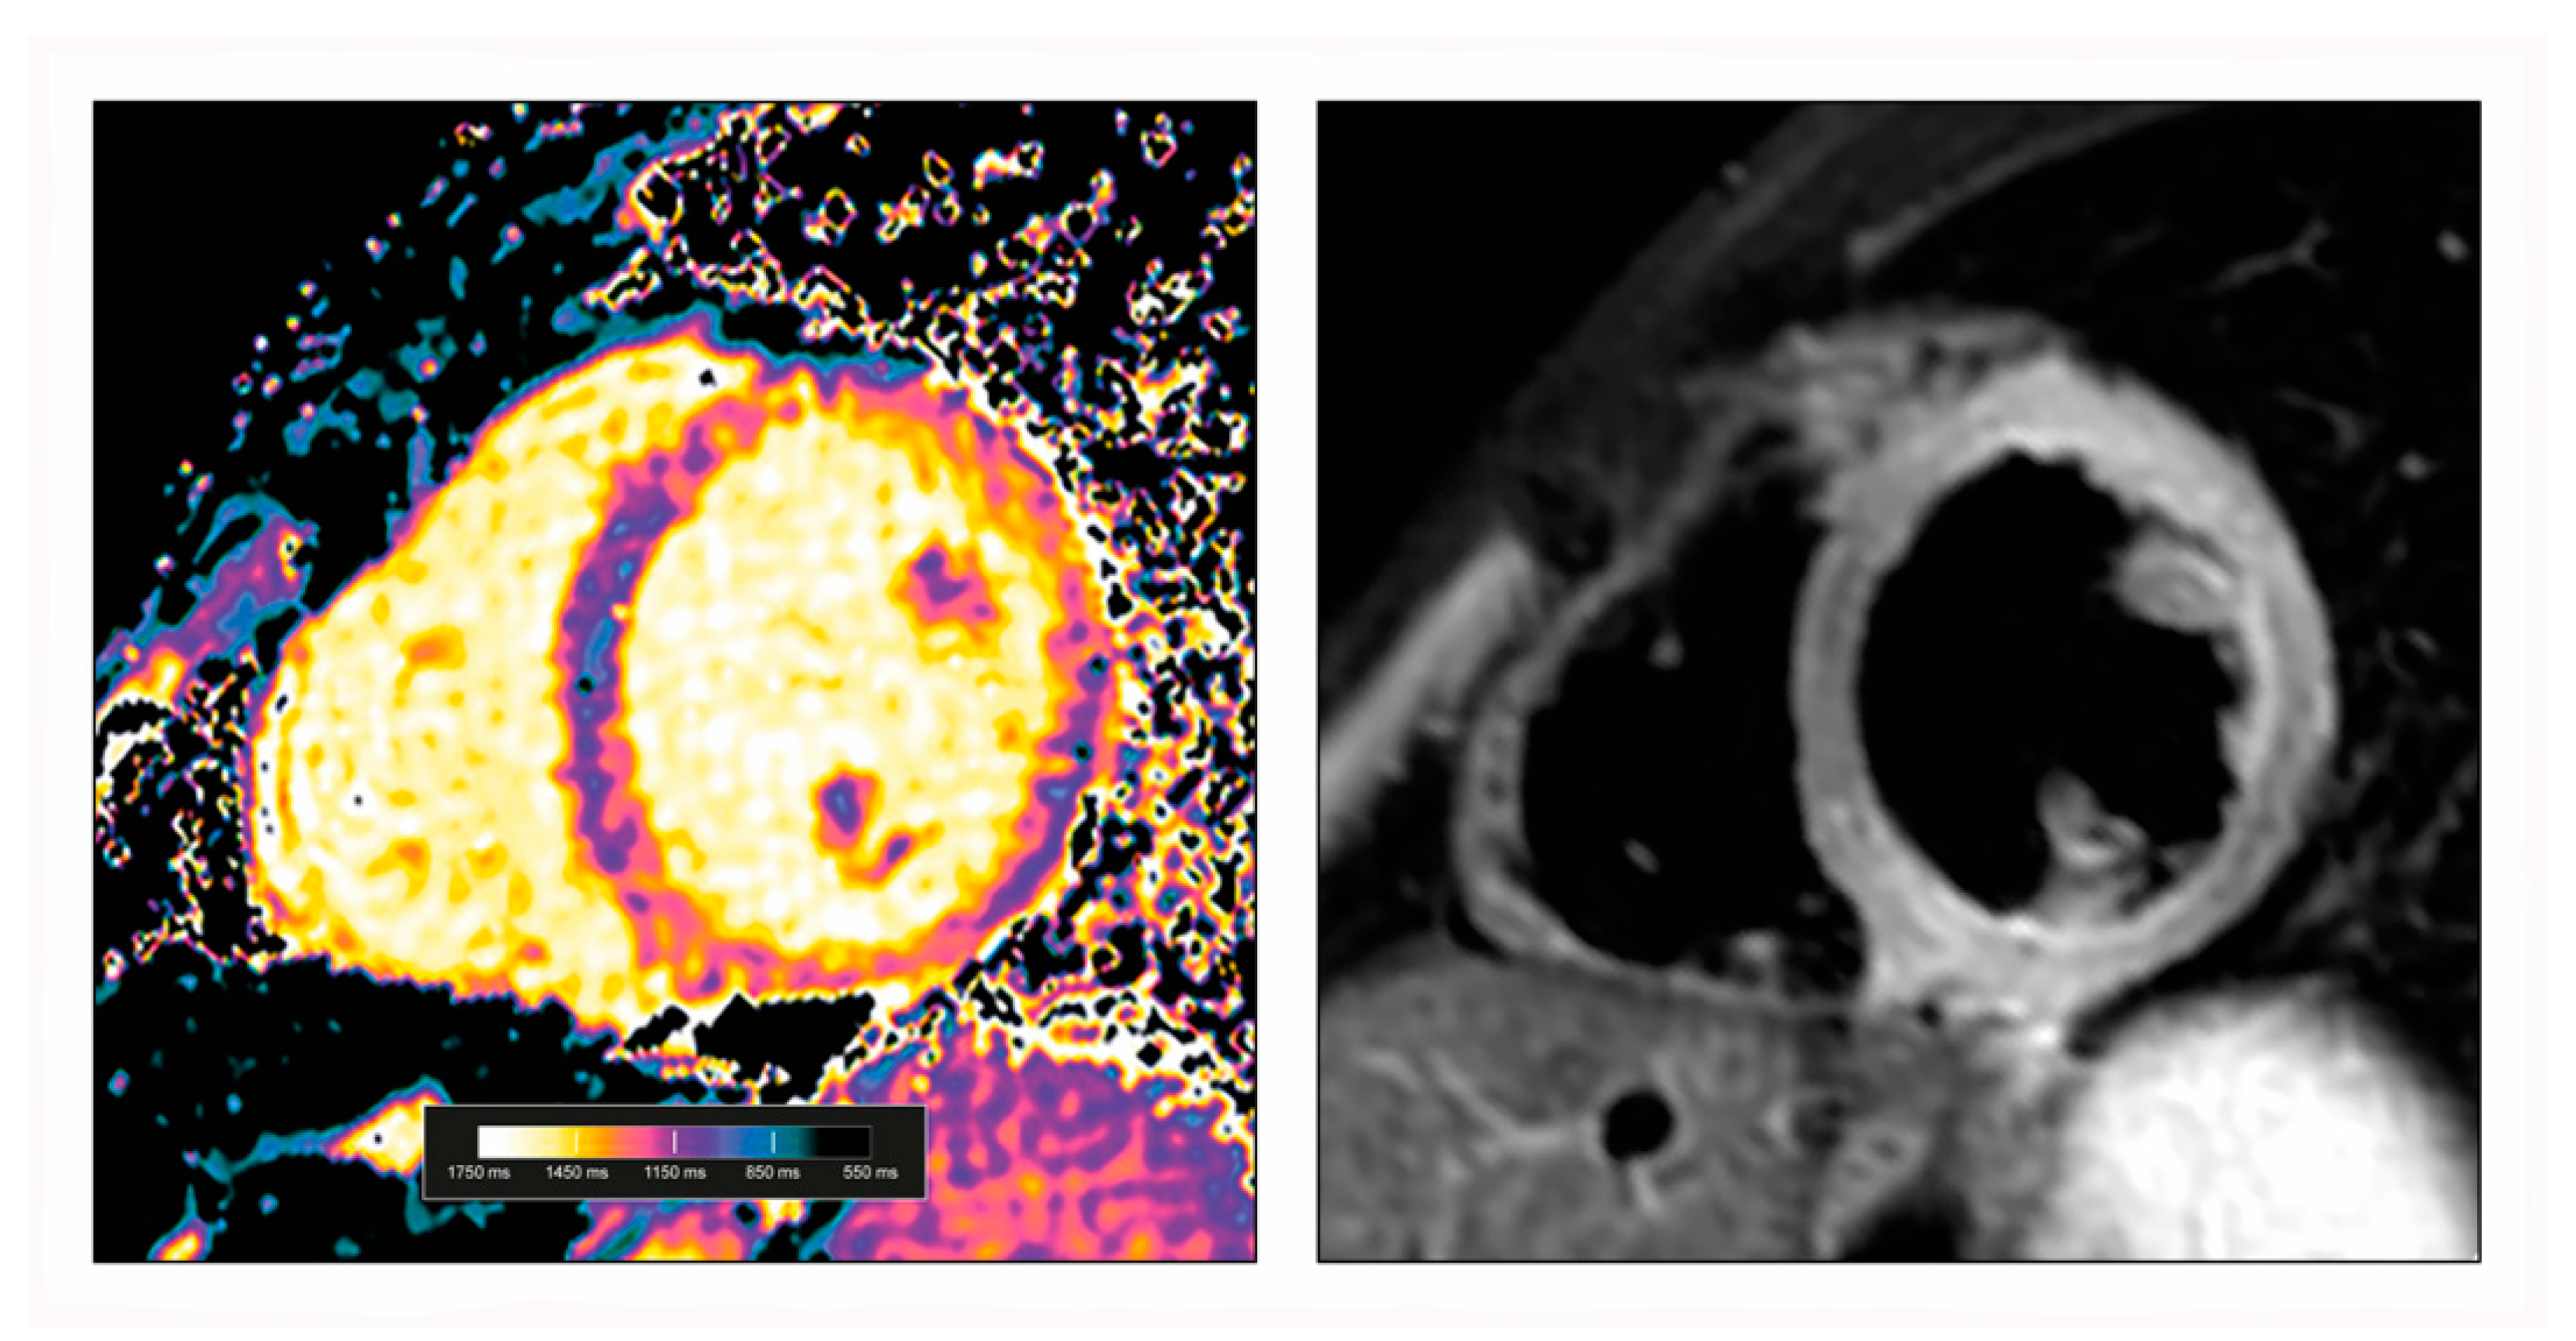

3.1. CMR Mapping Techniques

3.2. Myocardial Oedema